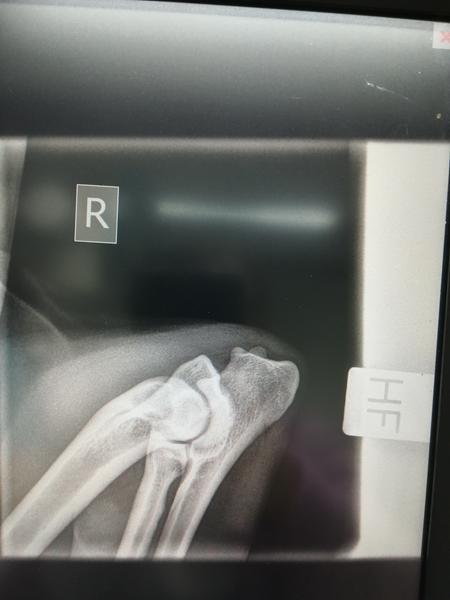

Til dem, der kan lide at vurdere HD/AD billeder {{forumTopicSubject}}

Iza's HD/AD billeder fra i dag.

Hvis nogen er glade for at vurdere den slags, er de velkomne med et bud.

Jeg skal nok skrive svaret fra DKK, når det kommer.

Men tænker du får a på de der hofter.

Men vil så(lidt pessimistisk) sige B/A, men tror nok mest på A/A.. Albuer har jeg ikke en anelse om, men de ser ud til at passe sammen, som de andre så fint siger også

Albuer 0

Iza's status kom i dag: HD A, AD 0